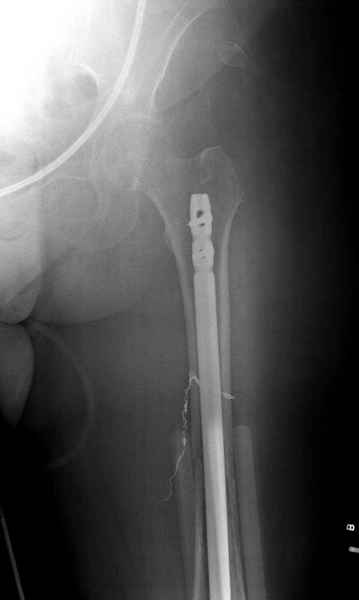

Для предупреждения кровотечения во время рассверливания, за день до операции провели эмболизацию сосудов питающий метастаз. http://radiology.rsnajnls.org/cgi/reprint/150/3/673.pdf (7-11, 12-15-16)

С минимальным рассверливанием и ретроградным методом провели остеосинтез бедра 12 мм гвоздем. (17-20)

Кровопотеря во время операции меньше 100 мл.